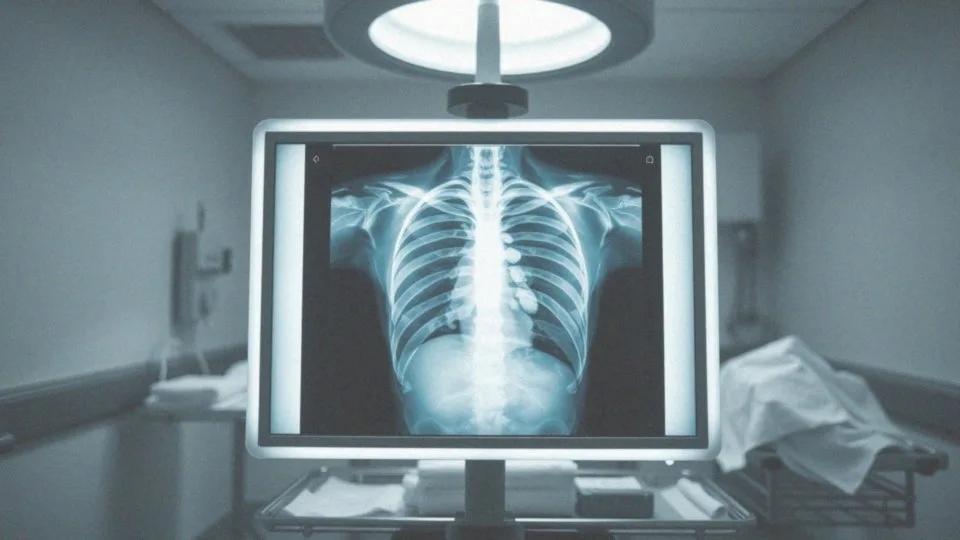

Istnieje wiele przyczyn tego urazu – poza mechaniką, warto również zwrócić uwagę na nadmierny skurcz mięśni odpowiedzialnych za oddychanie. Jeśli istnieje podejrzenie złamania, niezbędne jest zbadanie pacjenta, które zazwyczaj przeprowadza się za pomocą rentgenowskiego obrazu. Leczenie koncentruje się na stosowaniu środków przeciwbólowych oraz zapewnieniu odpowiedniego odpoczynku. Proces regeneracji trwa zazwyczaj od 6 do 8 tygodni. Dodatkowo rehabilitacja może obejmować specjalne ćwiczenia oddechowe, które pomagają w uniknięciu problemów z płucami.

Właściwa diagnostyka, zazwyczaj polegająca na wykonaniu zdjęcia rentgenowskiego, jest niezbędna, aby skutecznie odróżnić złamanie od stłuczenia. W przypadku złamań konieczne jest często podjęcie leczenia oraz rehabilitacji, co zależy od ich ciężkości. Natomiast stłuczenia można zazwyczaj leczyć prostymi metodami, takimi jak:

Kiedy istnieje podejrzenie złamania żebra, podstawowym badaniem diagnostycznym jest rentgen klatki piersiowej (RTG). To szybka i skuteczna metoda, która pozwala ocenić stan kości oraz zidentyfikować możliwe złamania. W sytuacjach, kiedy zachodzi ryzyko uszkodzenia narządów wewnętrznych lub wystąpienia złamań z przemieszczeniem, warto wykonać:

Dzięki tym technikom uzyskuje się bardziej szczegółowy obraz struktur wewnętrznych, co jest niezmiernie ważne przy diagnozowaniu skomplikowanych urazów. Jednak diagnostyka złamania żebra nie kończy się tylko na obrazowaniu. Kluczowy jest również szczegółowy wywiad oraz fizyczne badanie pacjenta. Lekarz wnikliwie analizuje dolegliwości, lokalizację bólu i okoliczności, które mogły doprowadzić do kontuzji. Te informacje odgrywają istotną rolę w precyzyjnym postawieniu diagnozy.

Dodatkowo, w przypadku podejrzenia urazów serca, zaleca się wykonanie echokardiografii, która pomaga ujawniać ewentualne komplikacje. Wykorzystanie diagnostyki obrazowej jest kluczowe zarówno do potwierdzenia złamania, jak i do zaplanowania dalszych kroków w leczeniu.